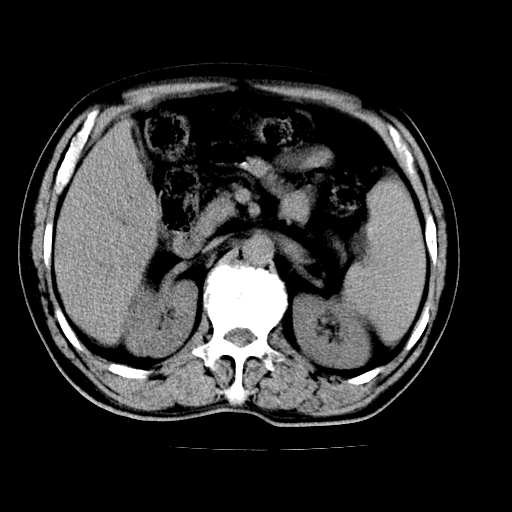

男,66岁,上腹部不适、黄染一周。彩超示:肝左叶占位,肝内胆管扩张,胆总管扩张,胆总管占位?

肝左叶不规则软组织肿块影,边缘不规整邻近肝实质受累分界不清;肝内胆管(左叶)明显扩张成“软藤状”,诊断:肝左叶胆管细胞癌。

肝左叶占位性病变,并胆管扩张,符合胆管细胞癌ct表现,门脉左支受累,左肾囊肿。窗宽太窄了,其他的看不清

左叶胆管细胞癌累及胆总管,门脉左支受侵,慢性胆囊炎胆结石,左肾小囊肿

肝左叶不规则软组织肿块影,边缘不规整邻近肝实质受累分界不清;肝内胆管(左叶)明显扩张成“软藤状”,诊断:肝左叶胆管细胞癌。胆囊钙乳症。